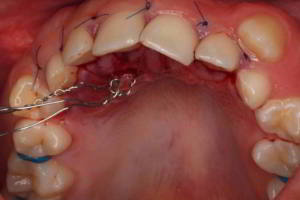

· Imagen 3, leer más...

La inclusión de los caninos superiores es la segunda más frecuente de todas las inclusiones dentales (por detrás de los terceros molares). Dentro de los planes de tratamiento de dicha inclusión, se puede optar, previa valoración general del caso, por extraerlo ante la imposibilidad de reubicarlo en su posición correspondiente en la arcada.

· Imagen 4, leer más...

Por otra parte, cuando se ha valorado de forma general y específicamente un caso de canino incluido, el tratamiento no tiene por qué ser tan agresivo y, no solo conservarlo, sino posicionarlo en su región correspondiente de la arcada. A este procedimiento se le llama “cirugía de rescate” y consiste en acceder a la corona del diente mediante cirugía y adherir un botón de tracción ortodóncica que irá paulatinamente orientando la posición del canino de forma armónica.